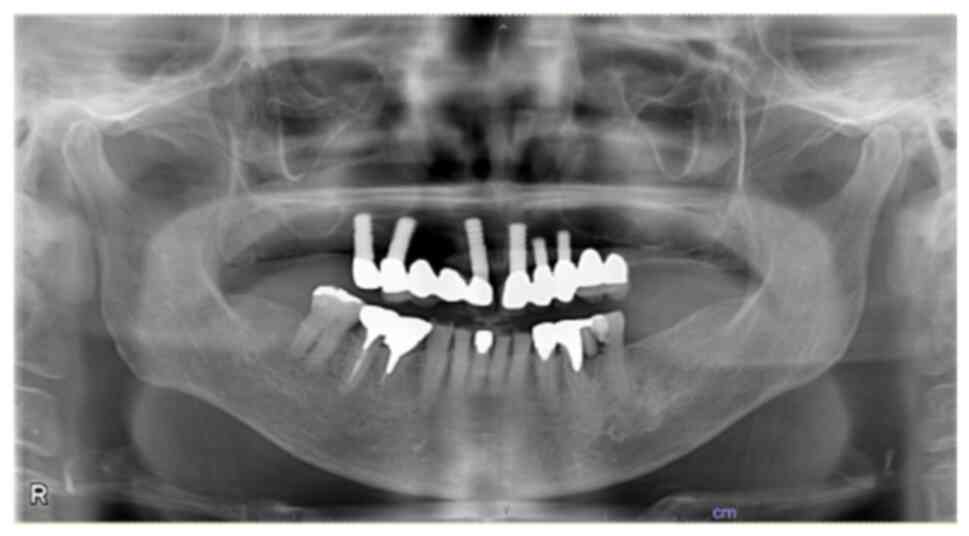

Methotrexate‑related other iatrogenic immunodeficiency‑associated lymphoproliferative disorder (MTX‑OIIA‑LPD) is prone to extranodal involvement but rarely involves the central nervous system (CNS). The present study reports a case of MTX‑OIIA‑LPD of the CNS discovered during medication‑related osteonecrosis of the jaw (MRONJ) treatment in a 76‑year‑old woman with rheumatoid arthritis (RA). The chief complaint of the patient was bone exposure and pain in the right mandibular molar. The patient had been receiving MTX for RA and alendronate sodium hydrate for osteoporosis, followed by denosumab. Treatment was initiated based on a diagnosis of MRONJ. However, the patient experienced lightheadedness and floating dizziness afterwards. Examinations revealed scattered neoplastic lesions in the brain. The histopathological diagnosis was diffuse large B‑cell lymphoma. A systemic search also revealed adrenal involvement. Since the patient was taking MTX, a diagnosis of MTX‑OIIA‑LPD was made and MTX was discontinued. Chemotherapeutic agents were administered since the central lesions became symptomatic. The MTX‑OIIA‑LPD lesions in the brain and adrenal glands completely resolved 8 months after onset. The physical condition of the patient improved, and the bone‑exposed areas became epithelialized. Reports on MTX‑LPD in the oral and maxillofacial region are few, which may delay its diagnosis. Therefore, biopsy of oral lesions in patients with MRONJ who are taking MTX and collaboration with related diagnostic departments, such as rheumatology and hematology, must be done to initiate the diagnosis and treatment of extraoral MTX‑LPD.